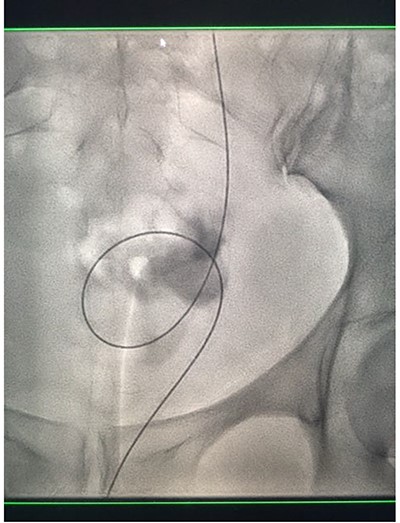

Under conscious sedation, using the previously inserted right percutaneous nephrostomy, antegrade access was achieved into the intrarenal collecting system and then into the proximal ureter. An 8 Fr × 11-cm access sheath was introduced. A guidewire was advanced antegradely through the site of ureteric transection and coiled in a position adjacent to the position of the guidewire that had been inserted retrogradely. A Gooseneck snare catheter was then passed over the guidewire and the snare was inserted (Figs 4 and 5). Under fluoroscopic guidance, the retrograde wire was retrieved and brought externally via the nephrostomy site, achieving through-and-through wire access (Figs 6 and 7).

Fluoroscopic images showing the retrograde wire successfully retrieved and brought externally via the nephrostomy site, achieving through-and-through wire access.